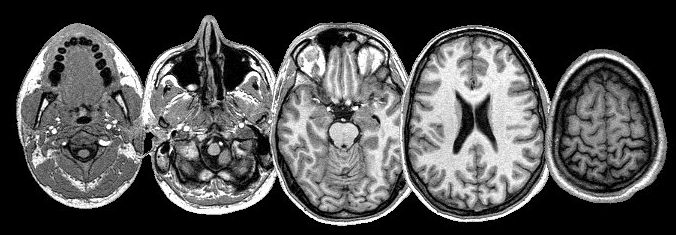

방사선, X-ray를 이용하는 것이 아니라 자기장과 컴퓨터 시스템 및 전파를 결합시켜서 CT 촬영보다 더 신체를 명확하고 분명하게 촬영해 고해상도 단면 영상을 만들어 낼 수 있습니다. 사람의 몸을 3차원으로 볼 수 있습니다.

CT MRI 촬영 차이점 중 큰 부분은 CT 촬영으로는 사람의 몸을 가로면으로 촬영할 수 있는데 MRI 촬영으로는 가로면과 세로면을 모두 촬영할 수 있어 좀 더 자세하고 세밀한 촬영이 가능하기 때문에 CT 촬영한 후 정확한 원인을 알 수 없거나 해서 더 자세히 봐야 할 경우 MRI 촬영을 하게 되기도 합니다.

또한 CT 촬영은 가로단면으로 촬영하기 때문에 복부 촬영에 좀 더 좋은 편이고 MRI 촬영 경우는 가로세로 함께 볼 수 있는 척추나 뇌신경계 촬영에 좀 더 좋습니다.